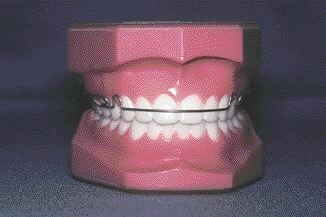

Self Learning, Self Assessment 2010 (September 01, 2010)

The SLSA program is based on current, referenced literature and consists of 40 questions, answers, rationales and references. Answers appear in the following issue at the end of each quiz. Dentists who complete the 15 question quiz in the November, 2010 issue of Oral Health may be eligible for continuing education points. The names and license numbers of all who complete the quiz will be forwarded to their respective provincial licensing authorities.